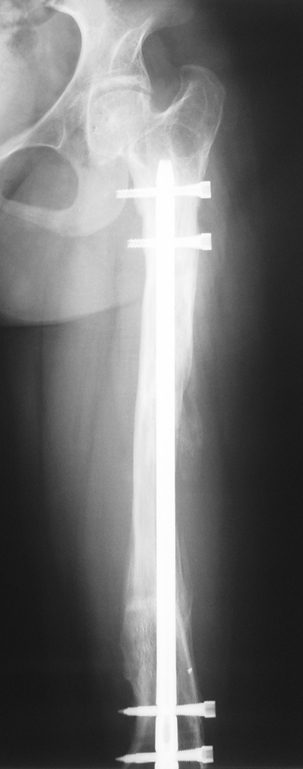

Bu Bacak Kısalık tipi bir kırığın kısalmış pozisyonda kaynaması ile oluşur. Bir çok vaka yetişkinlerde görülür ve sadece bir uzatma ile tedavi edilebilir. Ek deformiteler de aynı anda düzeltilebilir. Bu hastaların çoğu çivi üzerinden uzatma veya tam implante edilen çivi ile tedavi edilebilirler.